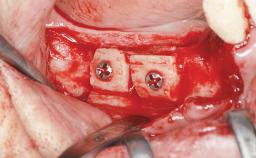

Autologous Iliac-Crest Graft for Anterior Blocks and Bilateral Sinus Floor Elevation in a Completely Edentulous Maxilla

A 56-year-old woman presented for treatment with complete edentulism of the maxilla. She had been using a complete removable denture since she was relatively young (age 30). Her chief complaint at presentation was lack of retention of the upper denture and a desire for a better restoration in order to improve retention, function, and esthetics. An initial clinical examination showed that the anterior maxilla was moderately atrophic both horizontally and vertically, also revealing a vertical deficiency of the posterior alveolar process. The mandible included natural teeth from 45 to 35, with previous extrusion of the anterior teeth that was being orthodontically treated. Also, there were two external hexagon dental implants at sites 46 and 36 that had been inserted elsewhere at a previous point in time. As the conditions in the mandible were healthy, including the teeth and the two implants, the patient had no complaints there.